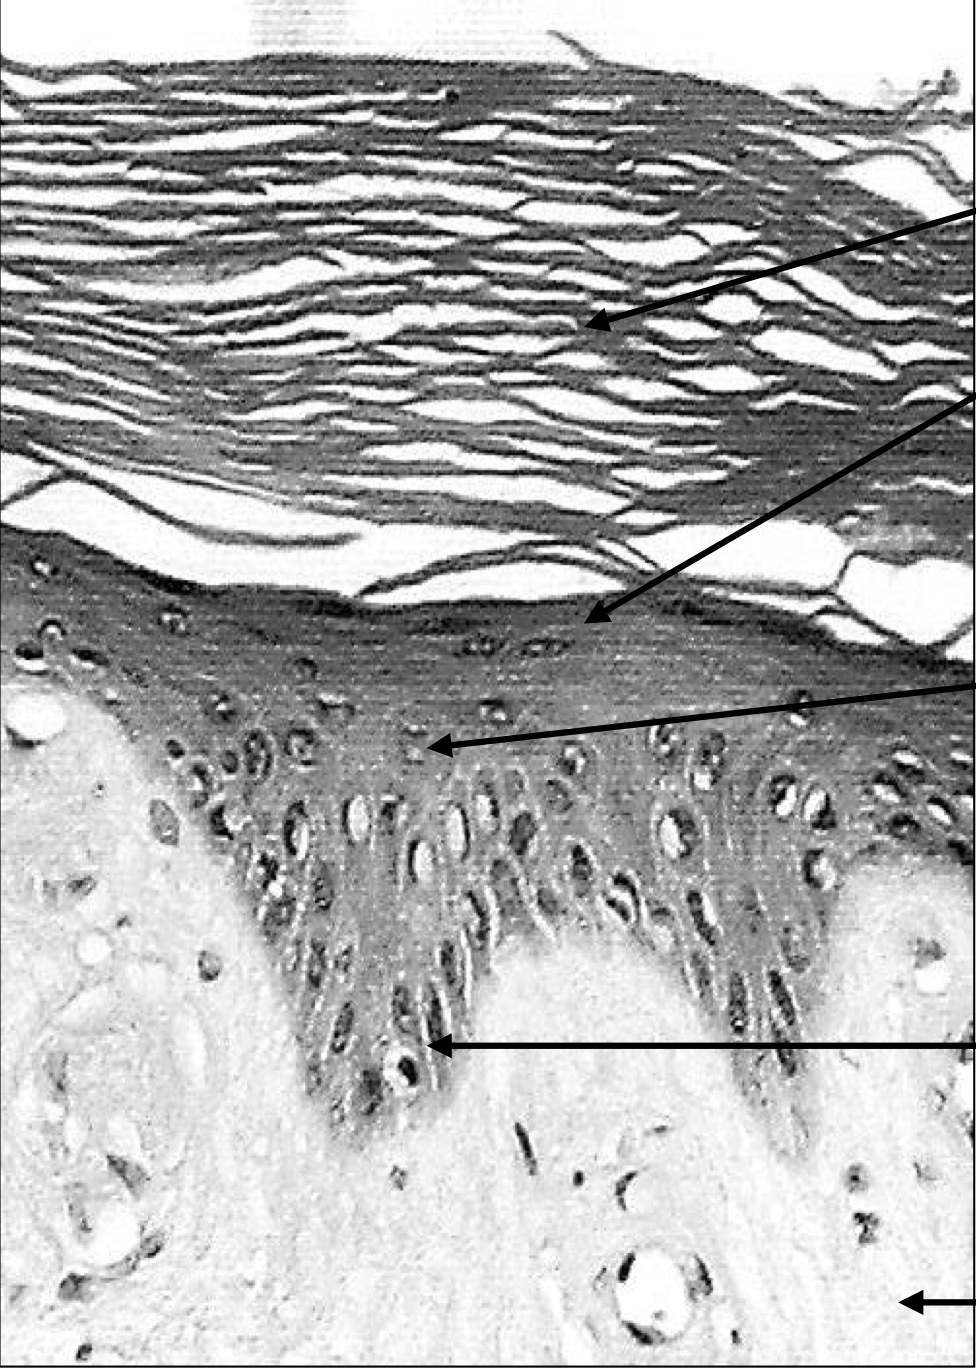

Explain the position of the basement membrane

It is a thin, flexible, acellular layer which lies between epithelial cells and the surrounding connective tissue

Explain the structure of the basement membrane

It is contributed to by the epithelial cells and the subtending connective tissue. Epithelial cells lay down the basal lamina. It’s thickness can be augmented by a variably thick layer of reticular fibrils (type III collagen), form the CT.

Explain the function of the basement membrane

It acts as a strong, flexible layer to which epithelial cells adhere. It also acts as a cellular and molecular filter. NB: the degree to which malignant cells penetrate the basement membrane is highly relevant to prognosis. NB2: the terms basement membrane and basal lamina are used inconsistently in literature